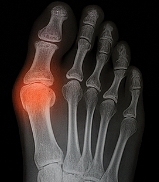

4. 영상 검사 (X-ray, 초음파, CT)

관절 변형, 토피(요산 결절), 염증 범위를 평가하기 위해 시행됩니다. 초음파에서는 관절 주변의 미세한 요산 침착도 확인 가능하며, CT는 장기적 손상 여부를 정밀하게 파악할 수 있습니다.